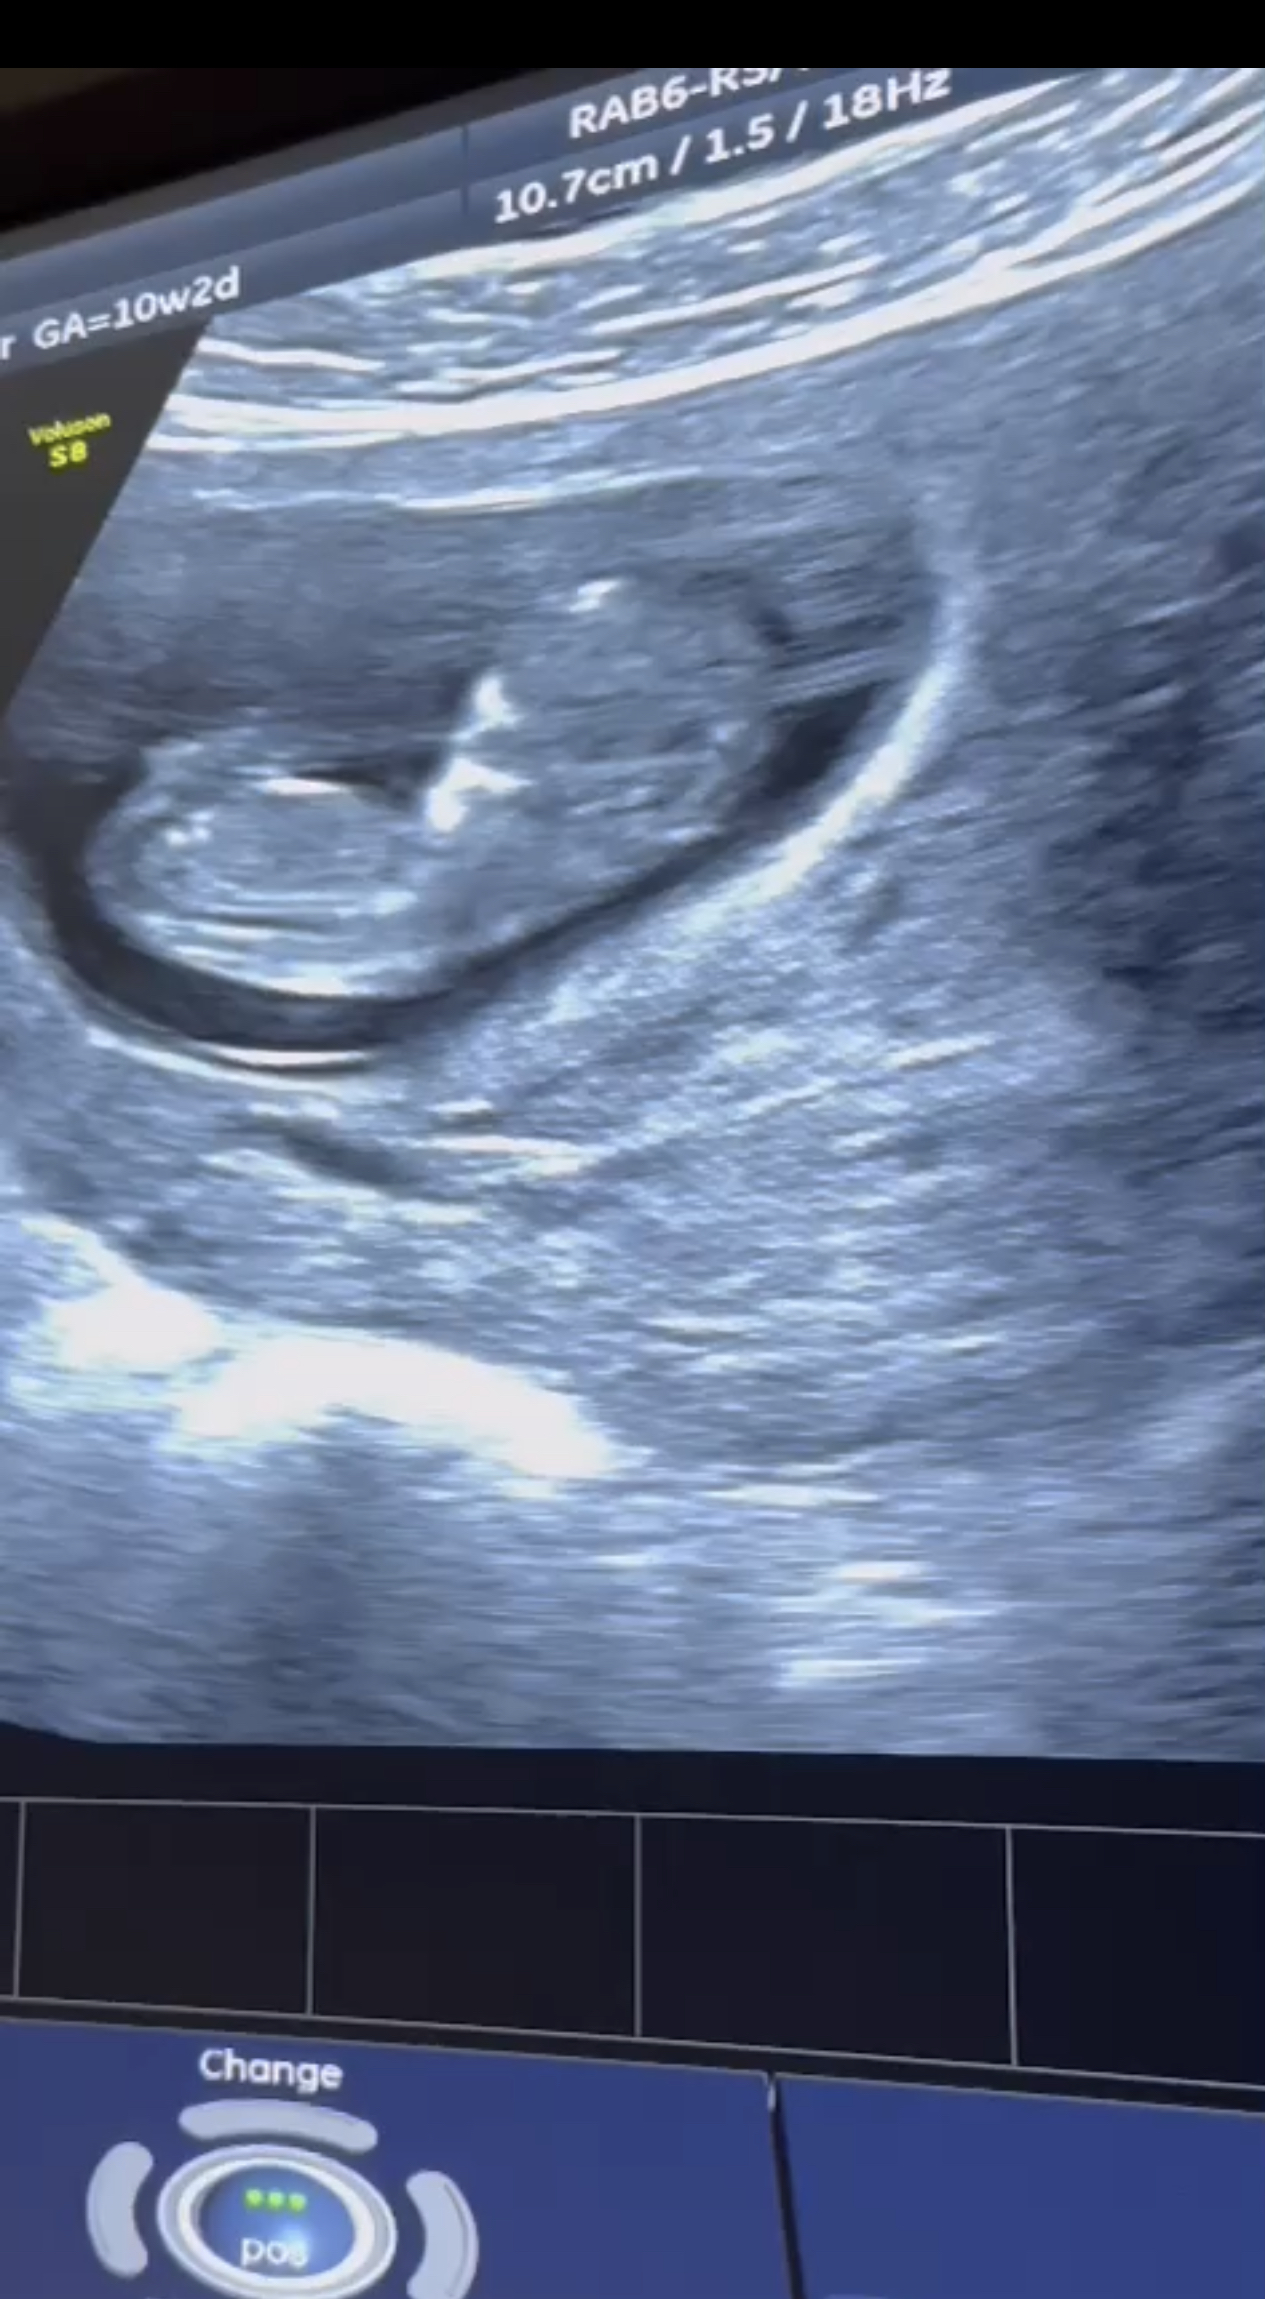

Ish-konkurenti i “Përputhen”, Beart Rexhepi po bëhet baba për herë të parë.

Ai ka postuar në Instagramin e tij një eko të bebit që do vijë në jetë, duke zbuluar në këtë formë lajmin e ëmbël.

“Prive” konfirmon lajmin se Bearti dhe e fejuara e tij do bëhen prindër për herë të parë së shpejti.

Kujtojmë që ai i propozoi për martesë të dashurës së tij, pak muaj më parë.